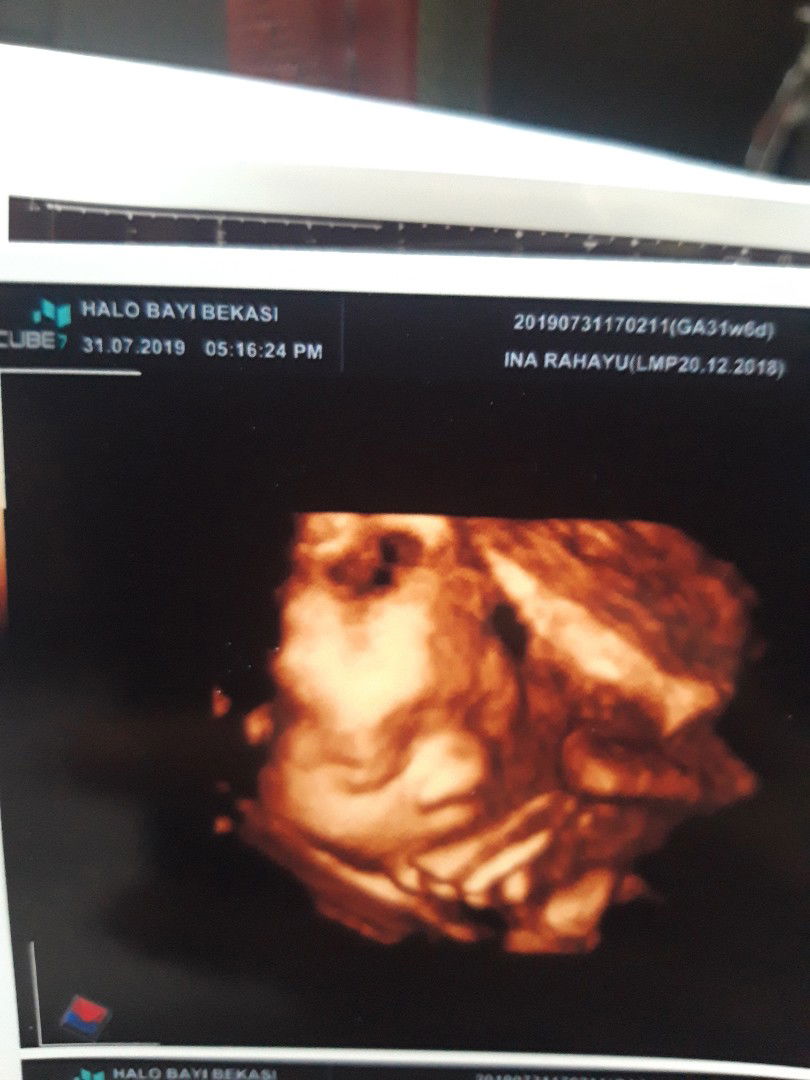

31w6day

Alhamdulilah pertama kali liat wajah ade setelah bbrpa kali ngumpet????